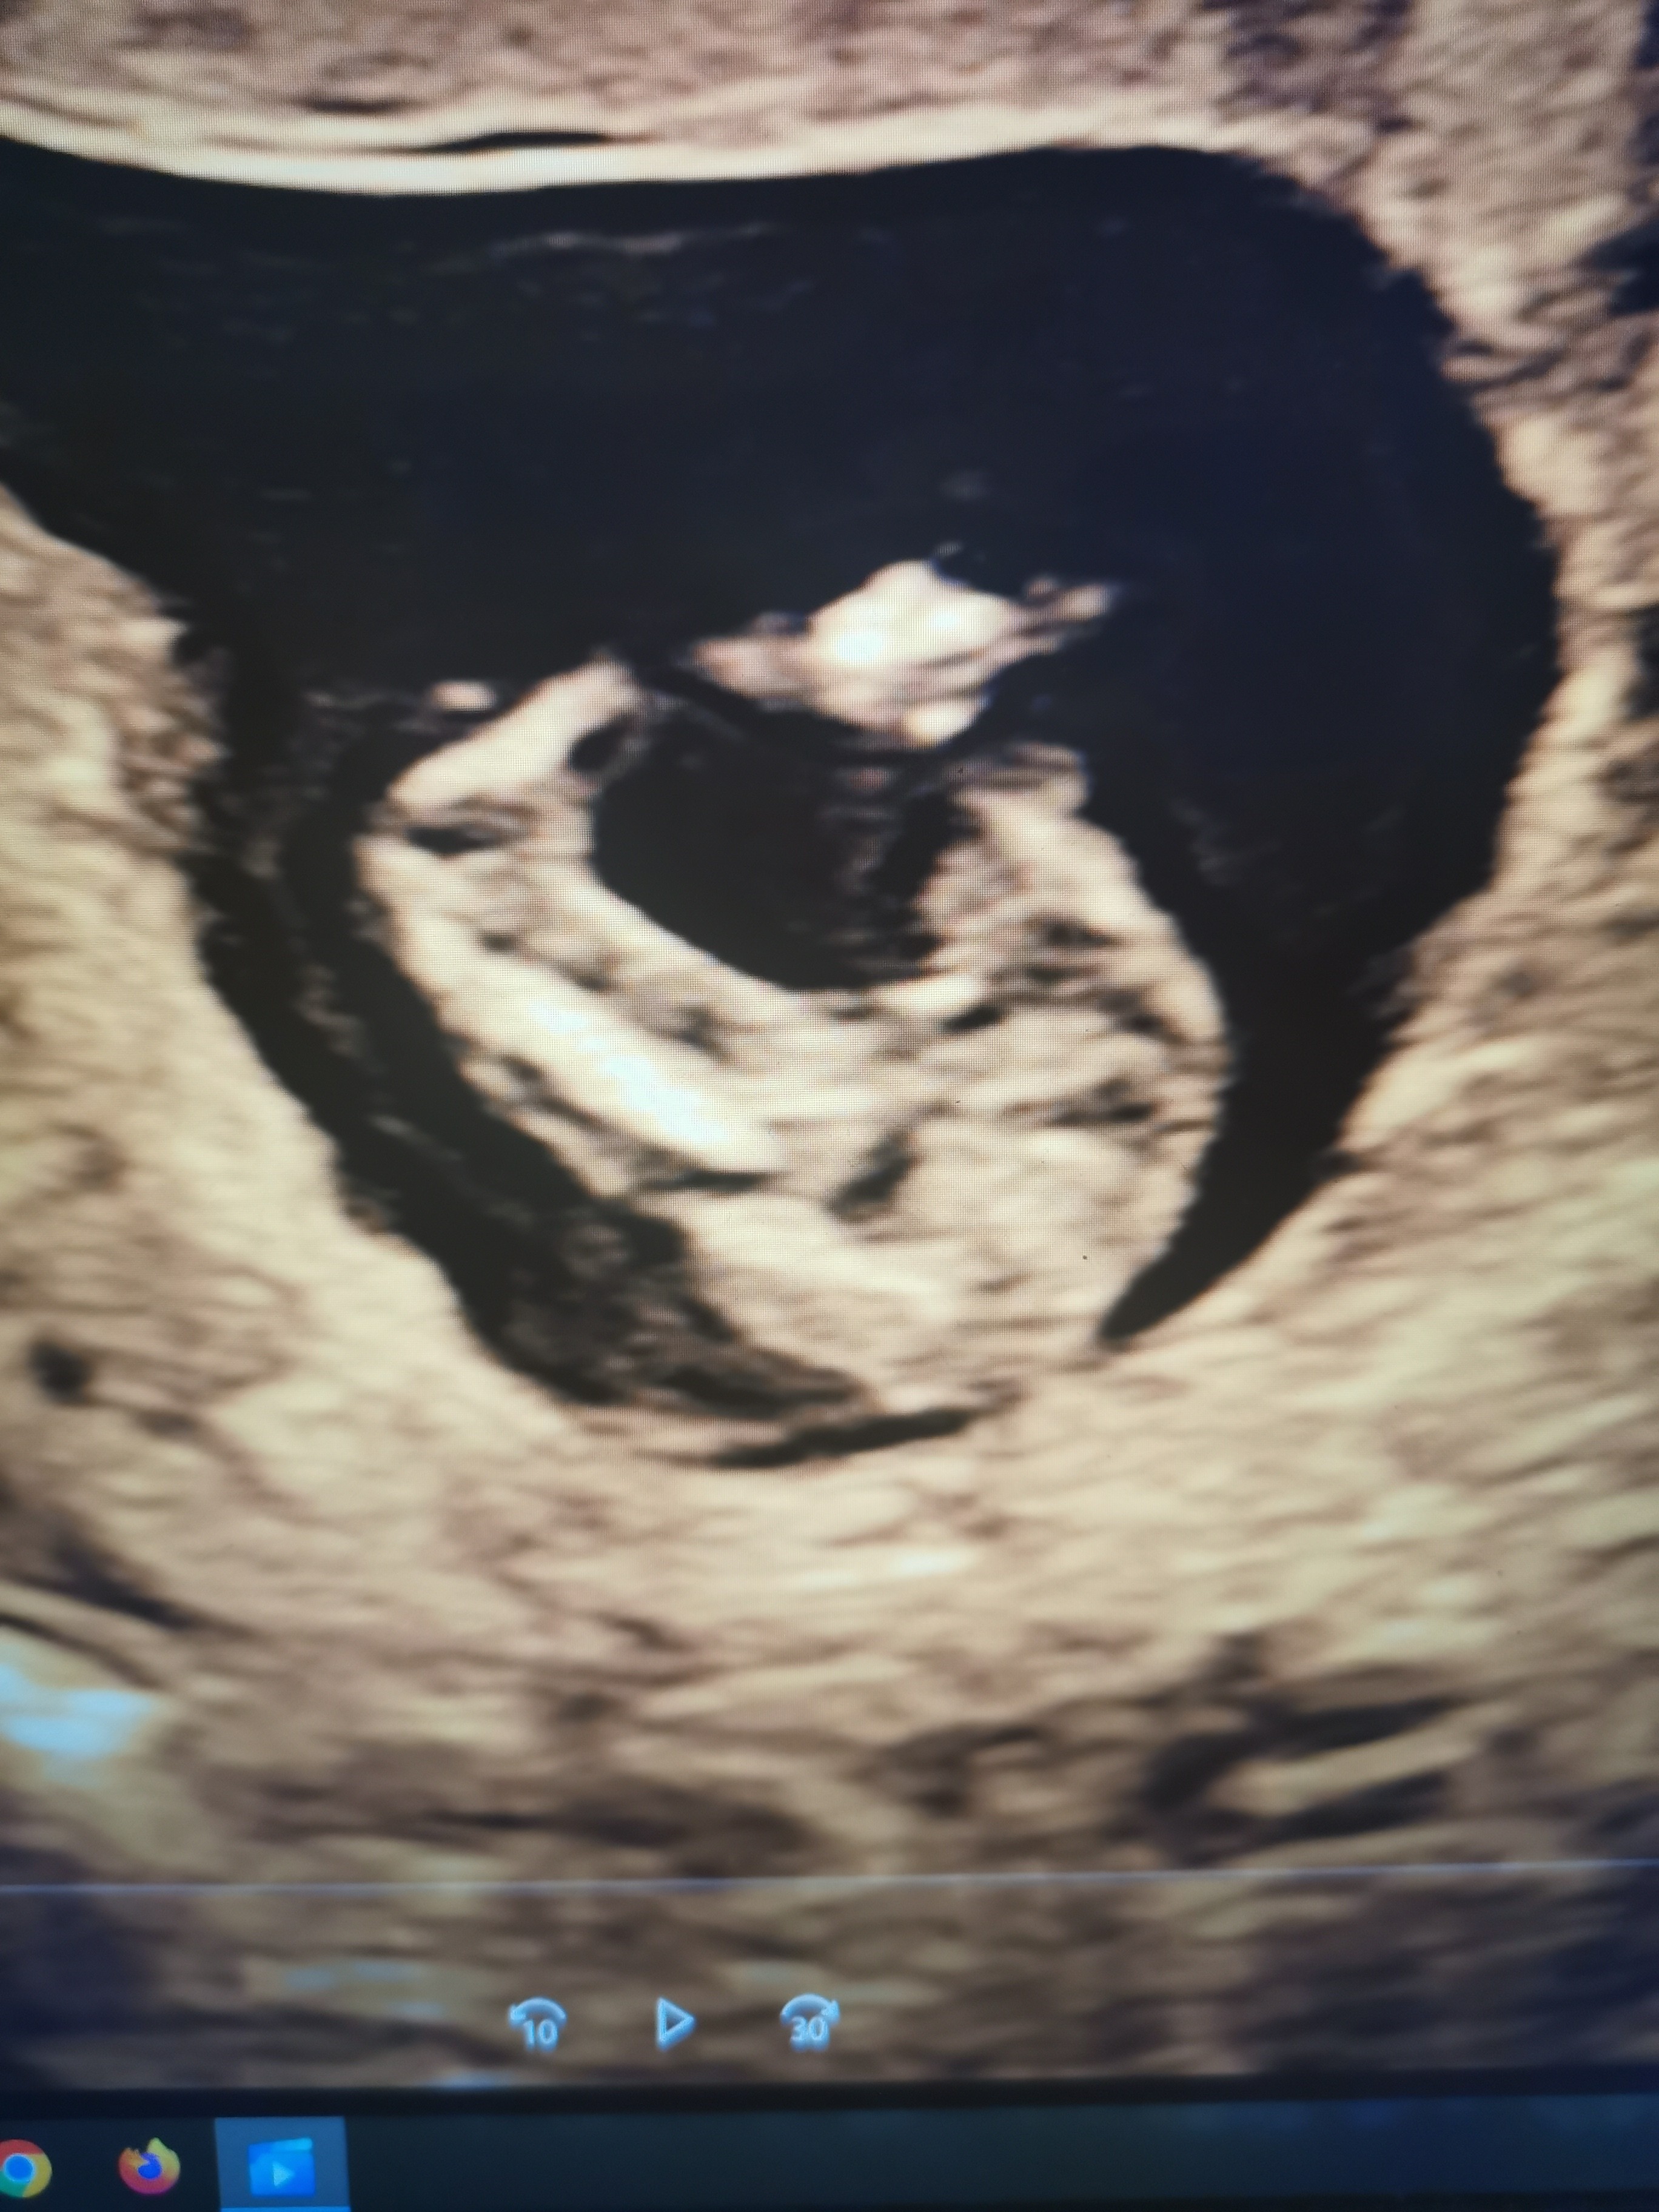

Dodaję fotkę bejbika i "jej" rozchylone nóżki 😂 Mam nadzieję, że to się nie wlicza w pornografię dziecięcą 😱😱

Załączniki

• IMG_20230111_210512_edit_2148259889900319.jpg

IMG_20230111_210512_edit_2148259889900319.jpg

1 MB · Wyświetleń: 102